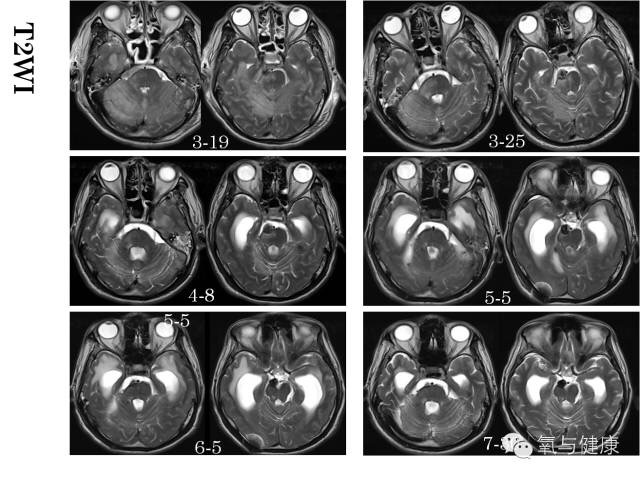

2014年3月12日下午5:20,北京天坛医院,一位男性患者,43岁,因突然出现昏迷,呼吸暂停正在紧急抢救。经紧急气管插管,呼吸机支持等抢救措施,待生命体征平稳后,急诊脑CT检查,确诊为颅内蛛网膜下腔出血,考虑动脉瘤破裂。于19:21分行脑血管介入造影,确诊为基底动脉尖夹层瘤破裂,并行动脉栓塞术。术后自主呼吸恢复,但仍呈浅昏迷状态,随后转入重症监护病房监护治疗,同时进行脑室和腰穿引流,颅内压监测。3月16日(术后第四天)患者昏迷状态加重,医院组织神经外科、神经内科、神经介入科、神经ICU和高压氧科等有关专家紧急会诊。经专家讨论认为再出血可能性很小,除加强监护治疗外,应尽早高压氧治疗。鉴于患者随后两日昏迷进行性加重,3月19日脑核磁影像发现右侧中脑、桥脑和小脑引部和半球广泛急性缺血改变,为挽救患者缺血区脑组织,改善脑干功能,随紧急于当日采用高压氧舱内抢救治疗。高压氧首次治疗后次日患者意识即出现明显好转,随后每次治疗后均有明显改善,后经经高压氧连续治疗6次后神志完全清醒,3月25日、4月8日及5月份脑核磁影像检查原脑缺血范围和程度明显好转(详见核磁影像对比)

3月19日患者意识障碍加重,脑核磁显示:小脑及右侧颞叶可见大片状水肿T2/FLAIR呈稍高信号,DWI呈稍高信号,提示小脑及右侧颞叶大片组织急性缺血性改变,无明显活动性出血;

3月25日和4月8日患者脑核磁复查显示:小脑及右侧颞叶可见大片状水肿T2/FLAIR呈稍高信号,DWI呈稍高信号逐渐减低,范围逐渐缩小,4月8日时DWI信号恢复正常。